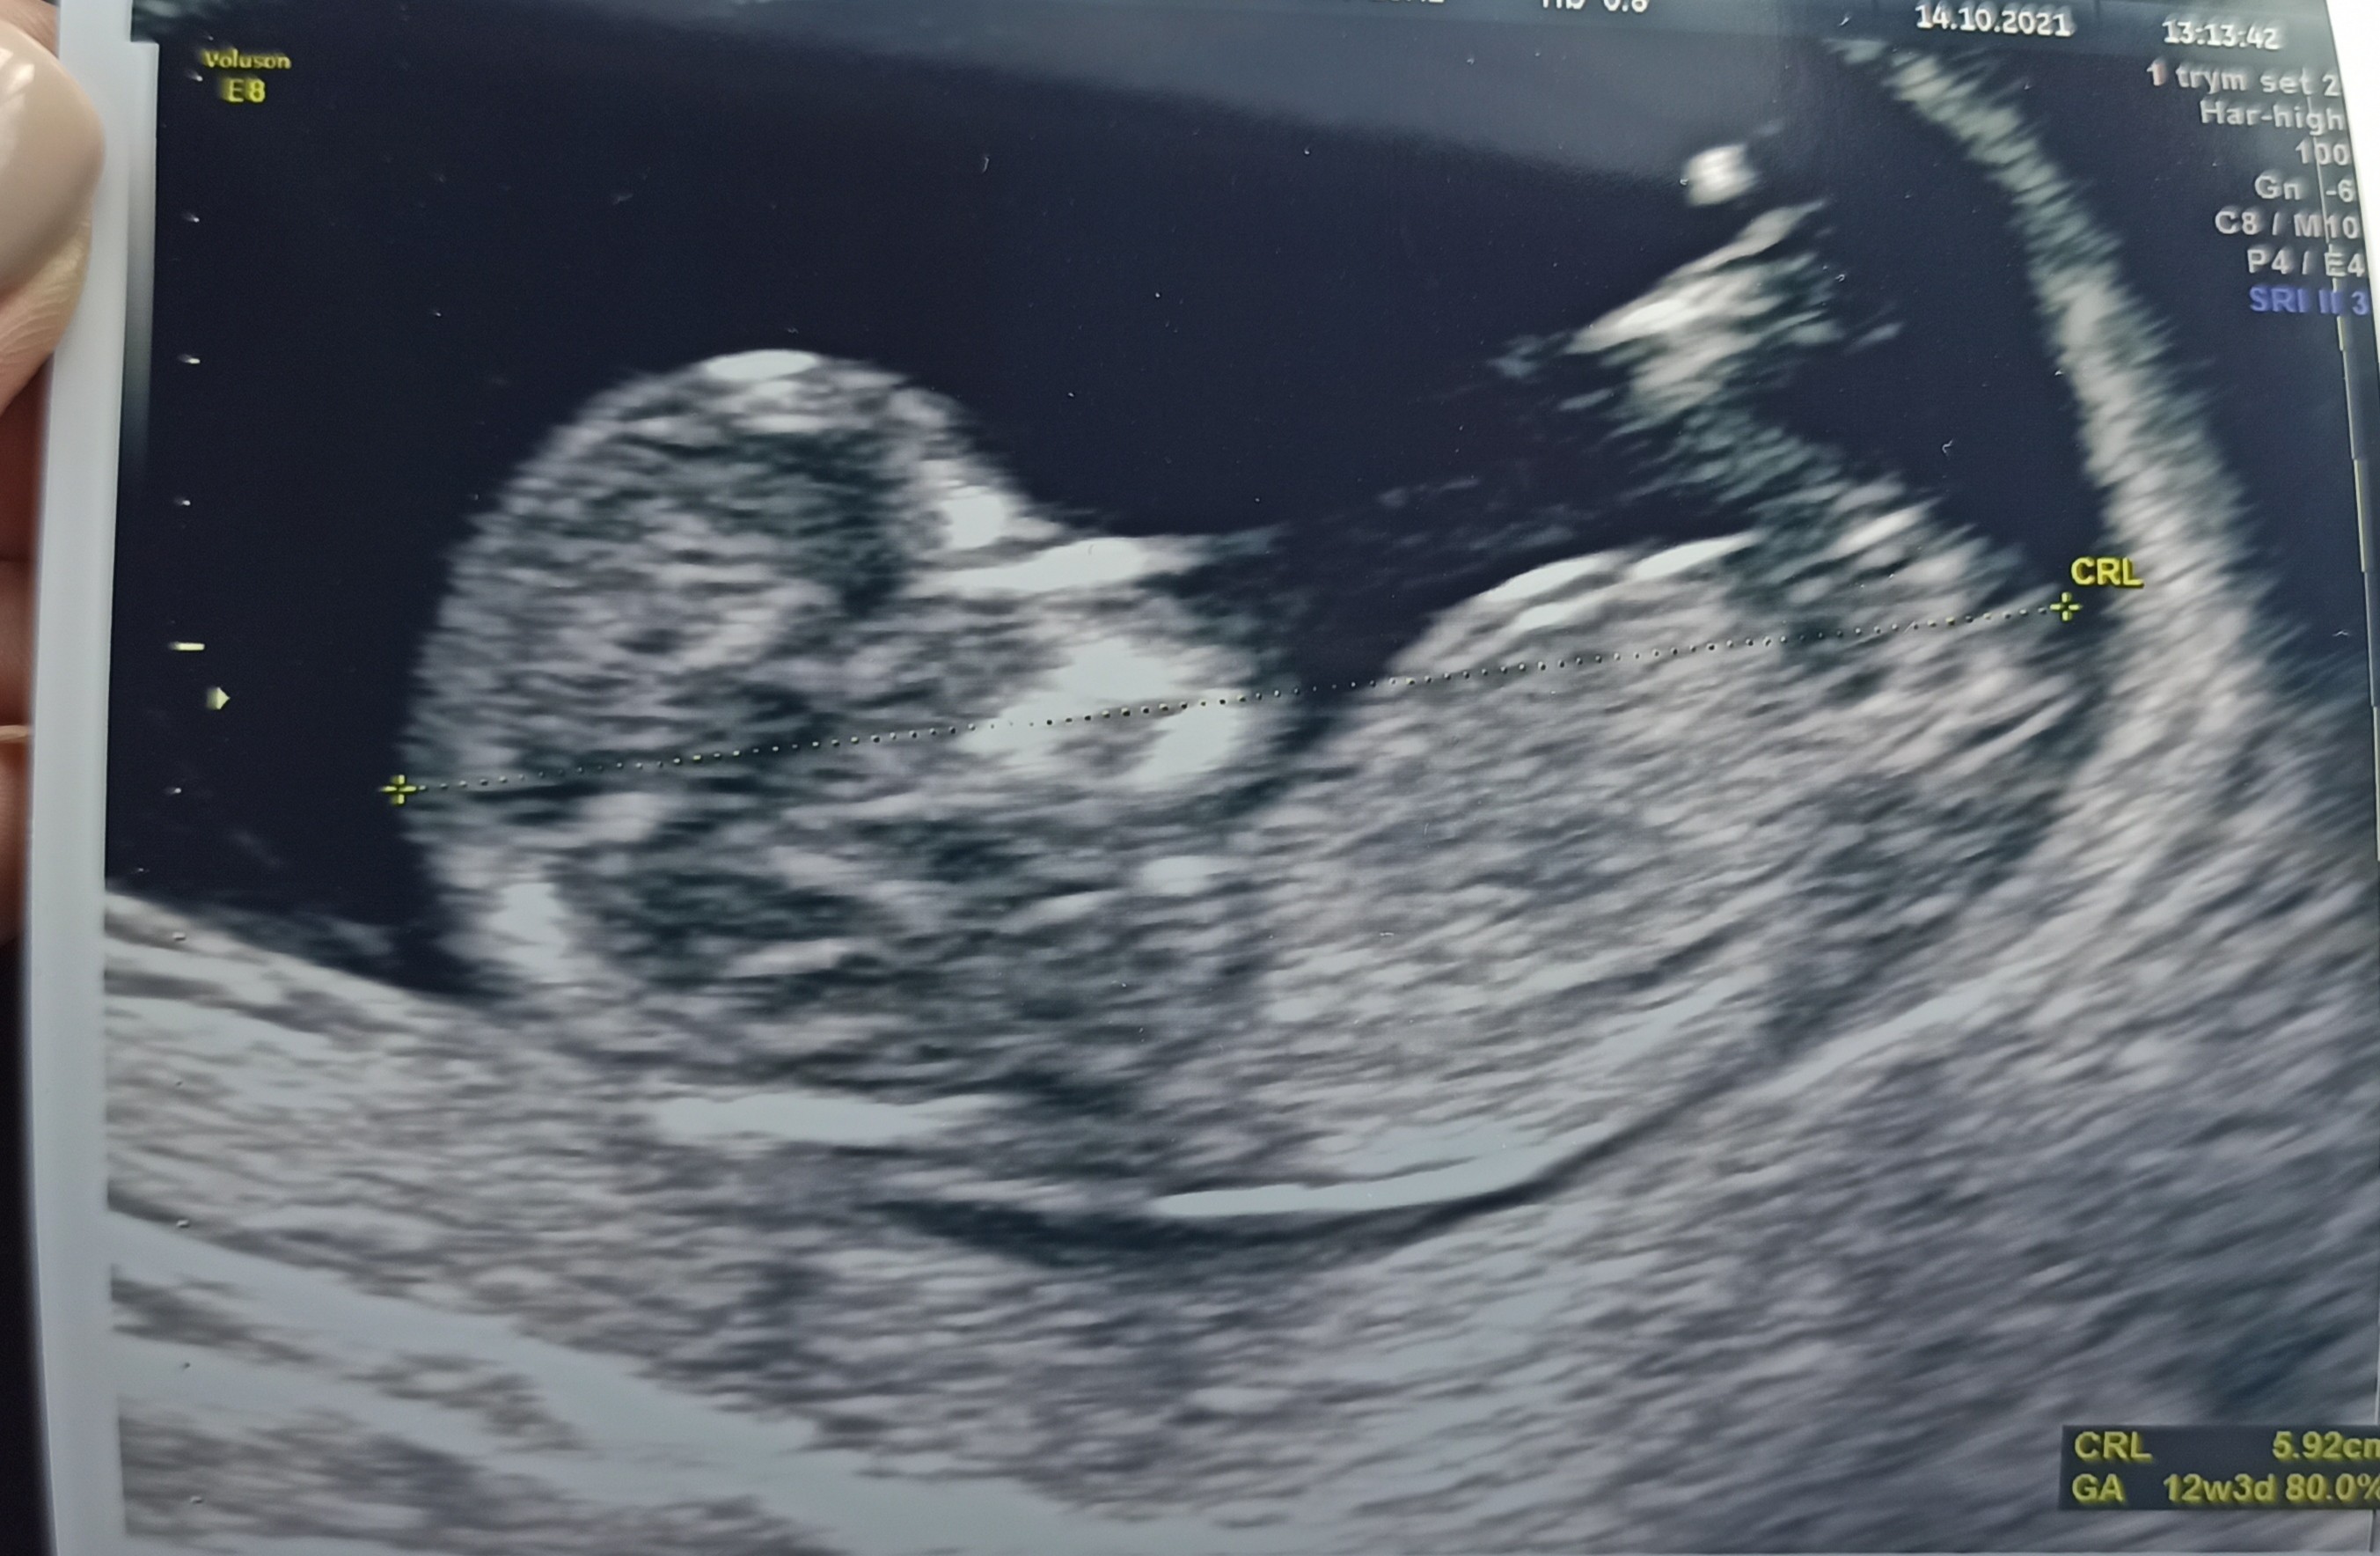

Dziewczyny też chciałabym się pochwalić swoim maleństwem. Zdjęcie z 12+3 z prenatalnych.

Obecnie jestem 14+3:)

Załączniki

• IMG_20211029_143642.jpg